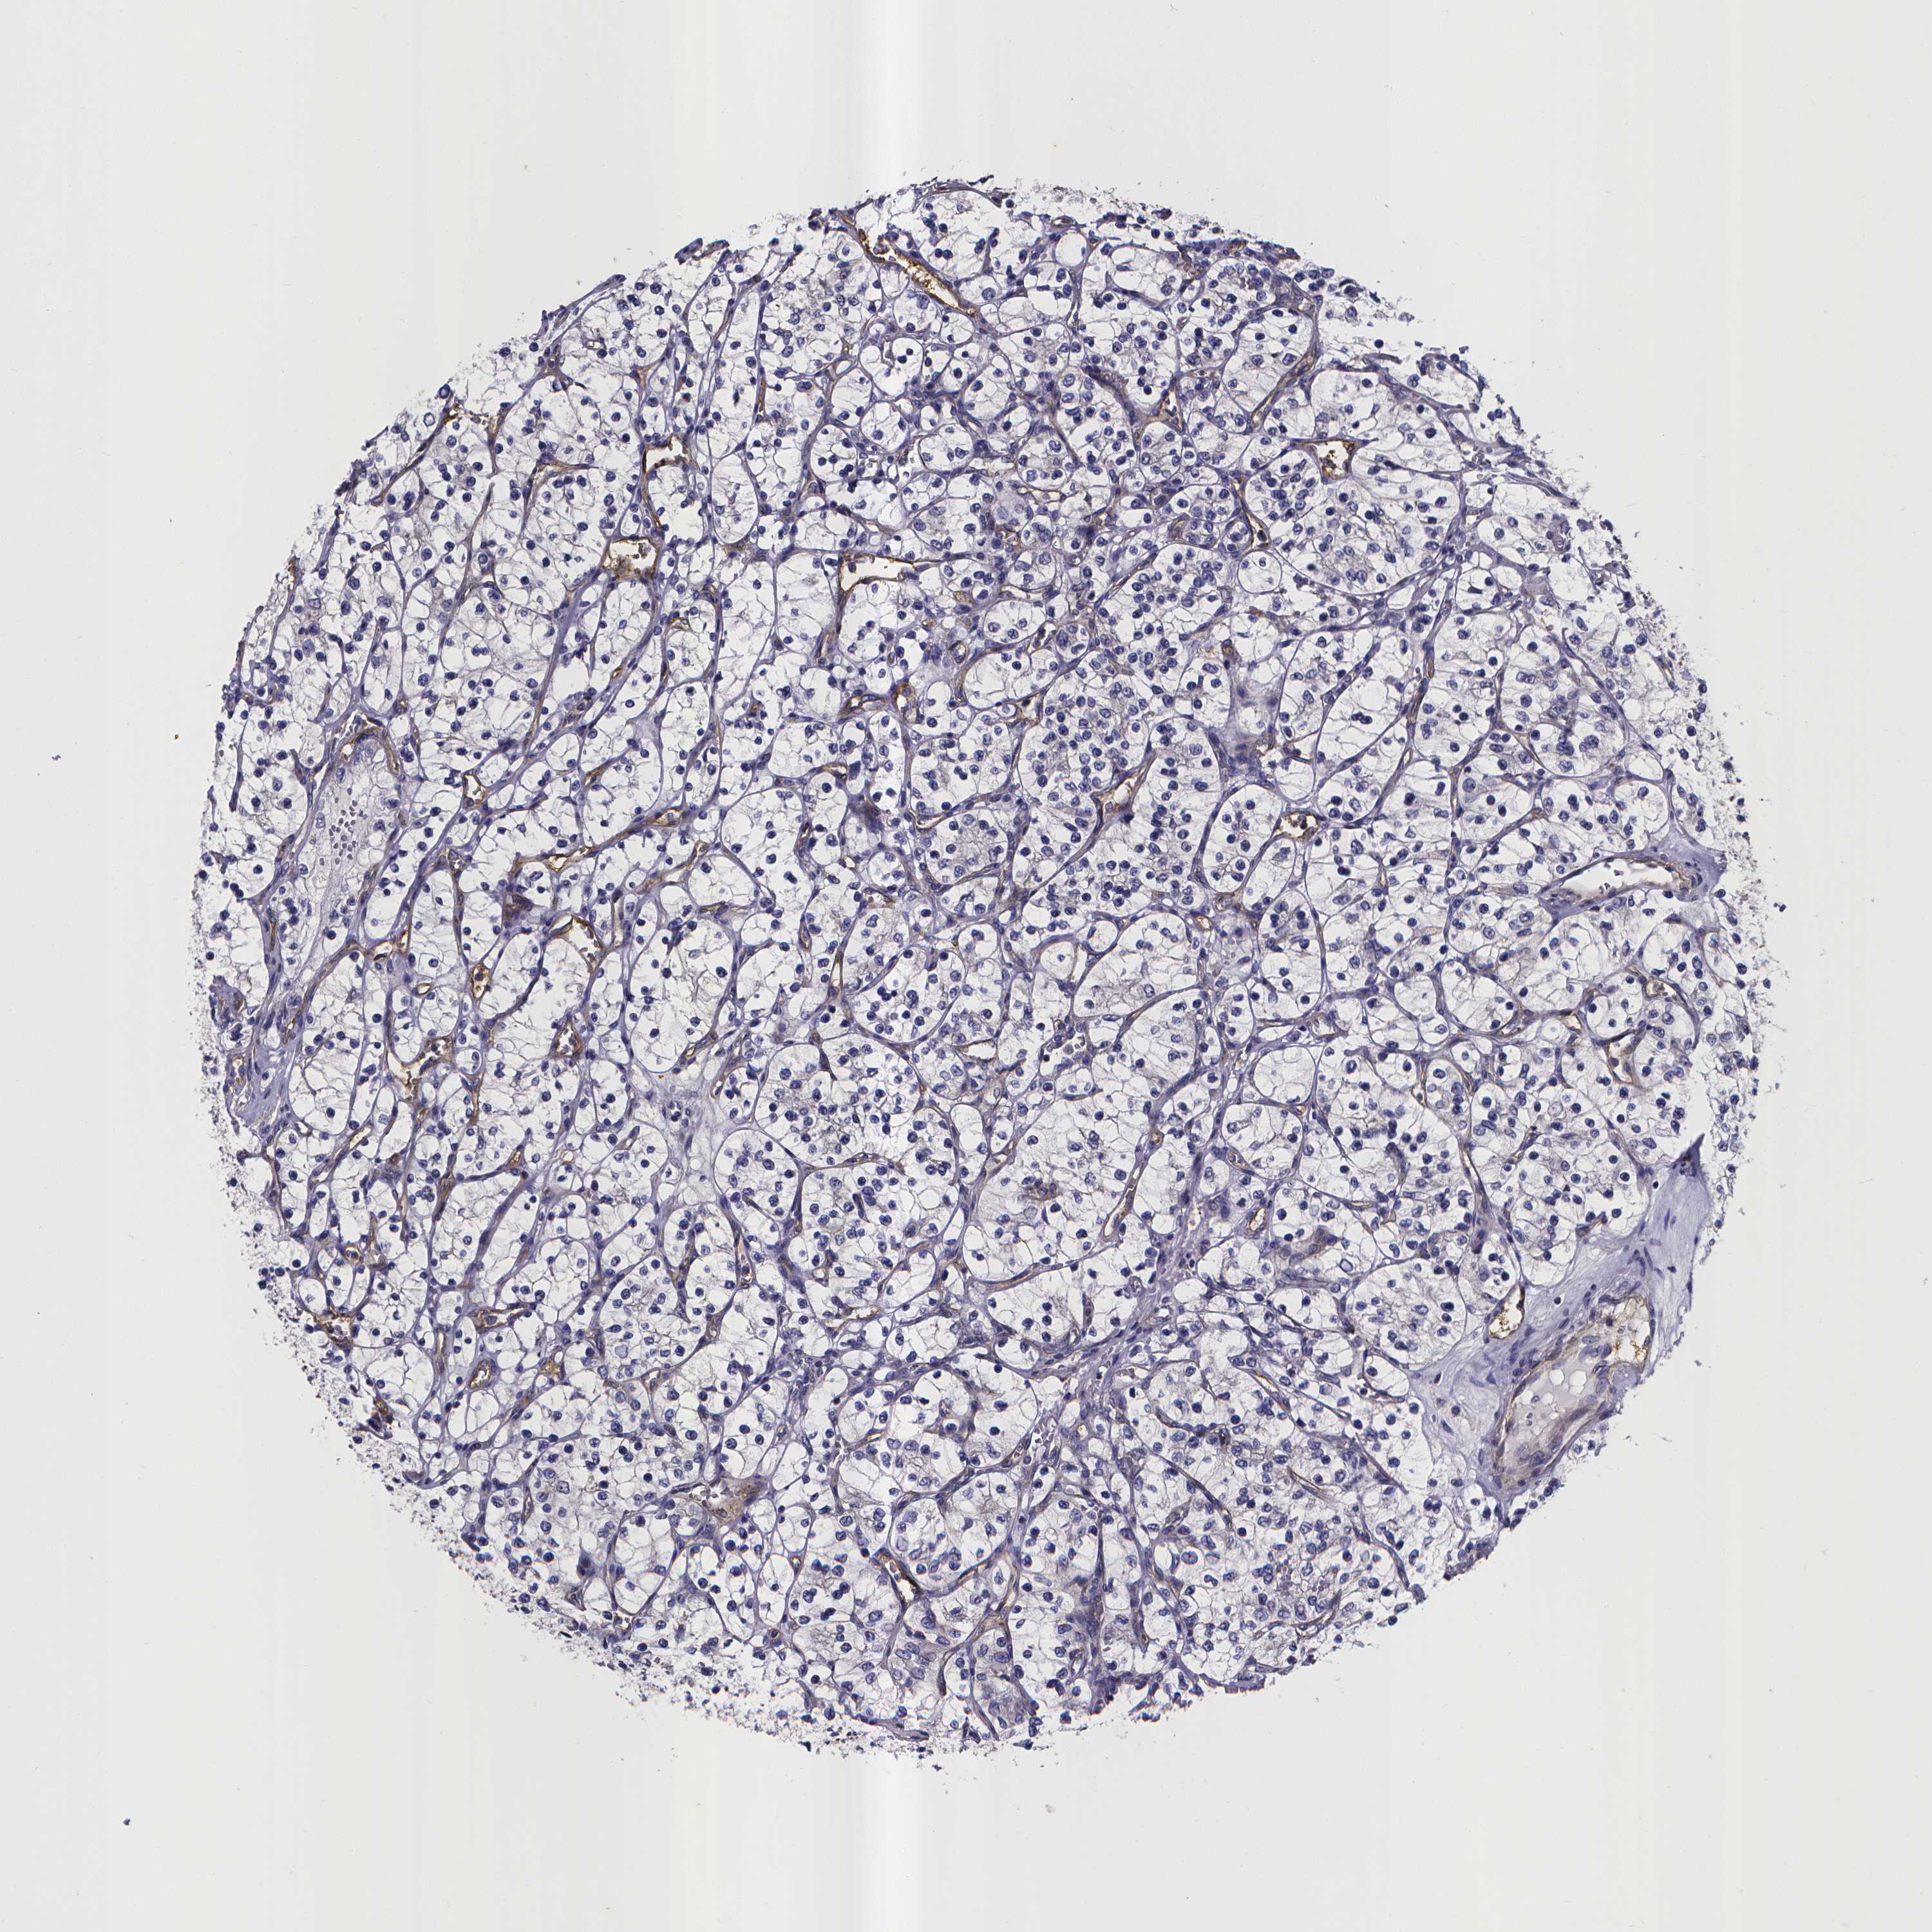

CANCER RENAL CANCER Show tissue menu

KICH TCGA KIRC TCGA KIRC VALIDATION KIRP TCGA PROTEIN RCC CPTAC PROTEIN EXPRESSION

Kidney renal papillary cell carcinoma